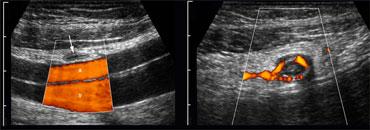

TRÁI: Ruột thừa bình thường có kích thước nhỏ, có thể đè xẹp, không có tín hiệu Doppler và không được bao quanh bởi lớp mỡ viêm. PHẢI: Ruột thừa viêm có kích thước lớn, không thể đè xẹp và tăng sinh mạch máu, được bao quanh bởi mô tăng âm, không thể đè xẹp, đại diện cho mạc treo ruột thừa nhiều mỡ

Doppler năng lượng cho thấy tín hiệu mạch máu thưa thớt hoặc không có, và không có lớp mỡ viêm tăng âm, không thể đè xẹp xung quanh ruột thừa.